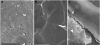

Fig. 3

Scanning electron microscopy of SECs. (A) Sinusoidal endothelial cells cultured for 1 day after isolation from normal liver demonstrate fenestrae in sieve plates. (B) Sinusoidal endothelial cells cultured alone for 3 days lack fenestrae. (C) Sinusoidal endothelial cells cultured for 1 day after isolation from thioacetamide-induced cirrhotic liver lack fenestrae.